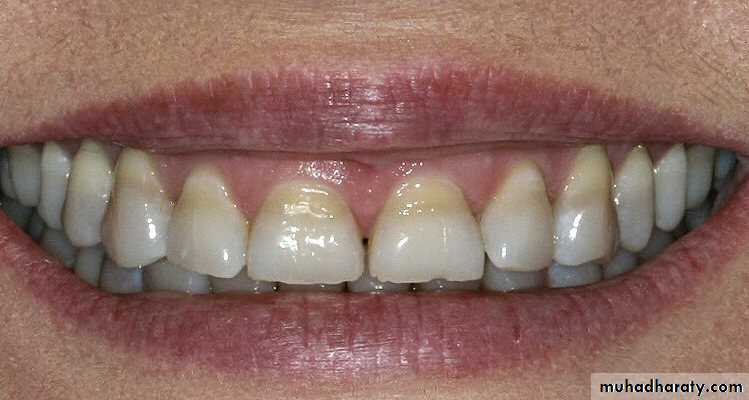

5. Incorrect Shade

Causes of an incorrect shade include:

1. Inappropriate operator lighting while selecting the shade.

2. Selecting the shade after the tooth is dried.

3.Shade tab not matching

the actual composite

Shade.

4. Wrong shade selected.

Potential solutions include:

1. Use natural light if possible.2. Select the shade before isolating the tooth.

3. Preoperatively place some of the selected shade on the tooth and cure (then remove).

• 4. Do not shine operating light directly on the area during shade selection.

• 5. Understand the typical zones of different shades for natural teeth.6. Poor Retention